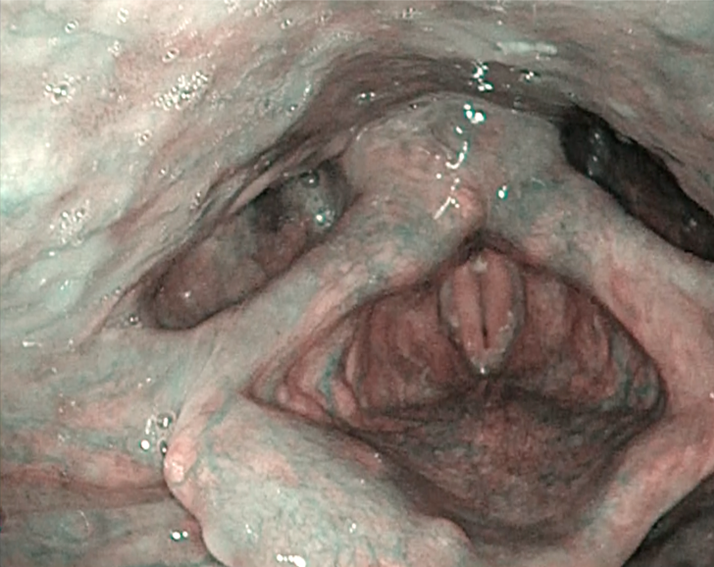

明るくコントラストのきいたNBI観察

高性能ランプや画像処理技術により、細かな血管や粘膜表層の視認性が向上しました。ノイズリダクション機能の性能も上がり、画像強調モードによる構造描写もよりクリアになりました。

画像強調モードの活用

血管構造の視認性向上により検査時間の短縮に貢献

ノイズの低減によって、画像強調を強めた状態でのストレスの少ない観察をサポート